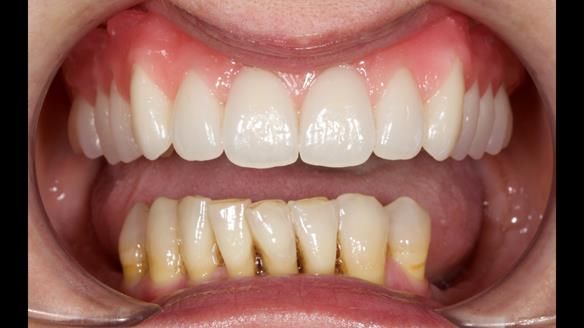

She had previously suffered from generalised periodontitis – stage IV, grade C, currently stable, with reduced attachment across the upper arch.

By the time she came to me, her periodontal condition was stable — but the aesthetics in the upper jaw were very poor.

We provided her with an immediate upper denture (Mk 1), followed by a definitive metal-based upper denture (Mk 2). A lower removable partial denture was discussed, to be made only if needed once the upper treatment was complete. However, at review, this wasn’t necessary — Adnana had excellent neuromuscular control and function, even with a shortened dental arch (SDA).

Rowan, Sam Hesketh and Chris Hesketh provided the stunning technical work. I am very lucky to have them.

- Immediate denture (Mk 1) fitted the same day the teeth came out

- Definitive denture (Mk 2), metal-based and custom-designed for her face

- A restored smile, restored lip support, and a patient who owned the journey